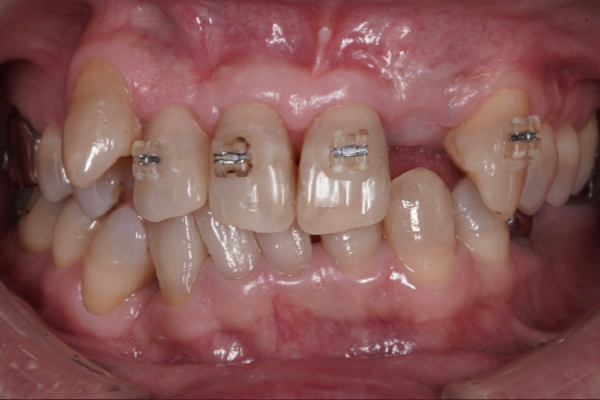

当院のインプラント治療例

― 他院で「難しい」と言われたケースにも対応 ―

※他院で骨量不足と診断された症例です。

【お悩み】

奥歯を失い、他院でインプラントの相談をしたところ「骨が足りないため難しい」と言われ、不安を感じて来院されました。

【診断】

歯科用CTにて詳しく検査を行った結果、インプラントを行うには骨量が不足している状態であることが確認されました。

【治療内容】

骨をつくる治療であるGBR(骨造成)を併用し、将来的な安定性を考慮したうえでインプラント治療を行いました。

【治療後】

現在はしっかり噛める状態となり、日常生活でも違和感なく食事を楽しんでいただいています。

【担当歯科医師からのコメント】

骨が少ないケースでも、CTによる診断と適切な治療計画によりインプラントが可能となる場合があります。

「難しいと言われた」とお悩みの方も、まずはご相談ください。